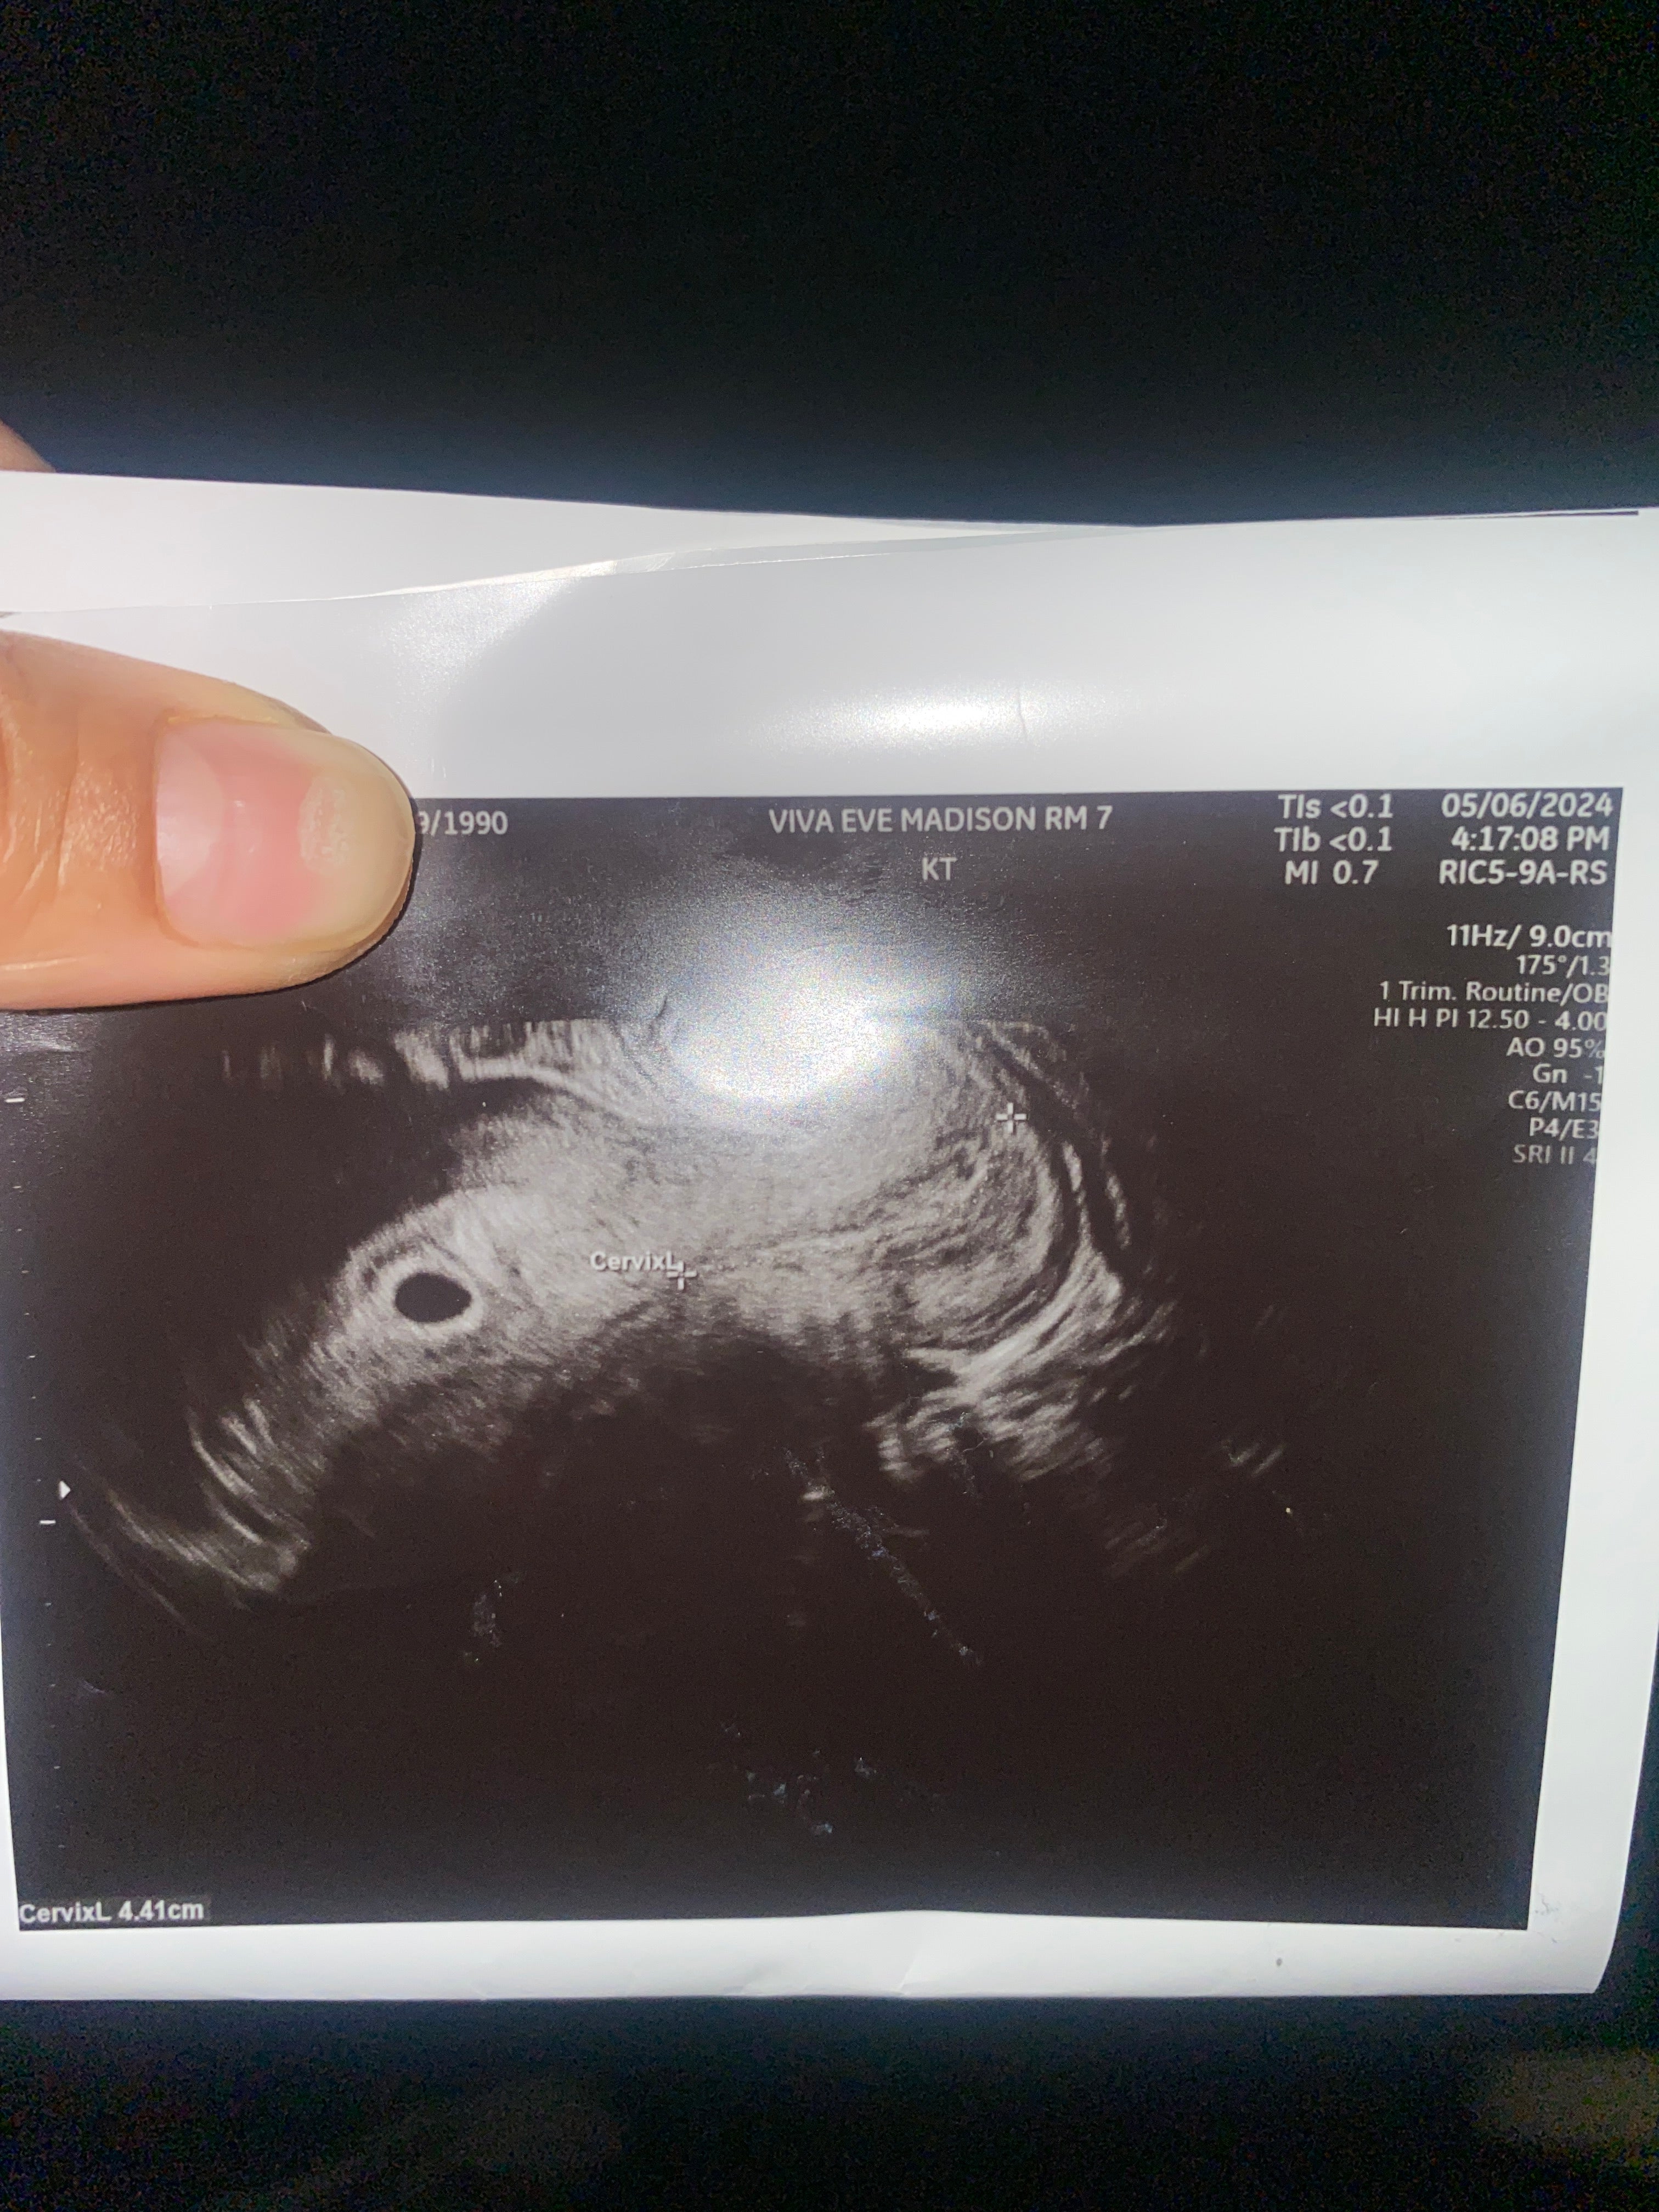

My husband and I have struggled to conceive due to my endometriosis and some scaring tissue that destroyed my right ovary and Fallopian tube. Luckily after a few surgeries I started to get better but was concerned IVF would be out of reach now that I have limited eggs. Mosie Baby made me and my husband have a chance at a normal pregnancy. I am currently now 5 weeks and 4 days pregnant! Thank you Mosie Baby!